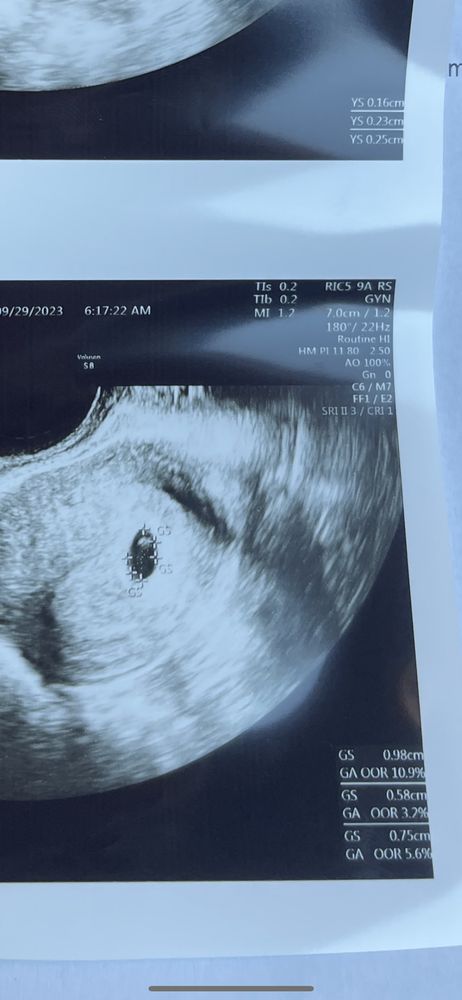

Нужен совет (вне обсуждений основной темы сообщества, но в рамках разумного)Девочки я в панике . 29.09 ходила на узи все ок , видно все . 14.10 иду говорят нет эмбриона . Срок 6 недель от зачатия . Через неделю сказали прийти . Я не хочу верить , для меня это страх .

Екатерина Галдина, я не знаю как посчитать правильно . Послание месячные были 17.08. . Зачатие было 31 августа или 1 сентября . На прошлом узи было так